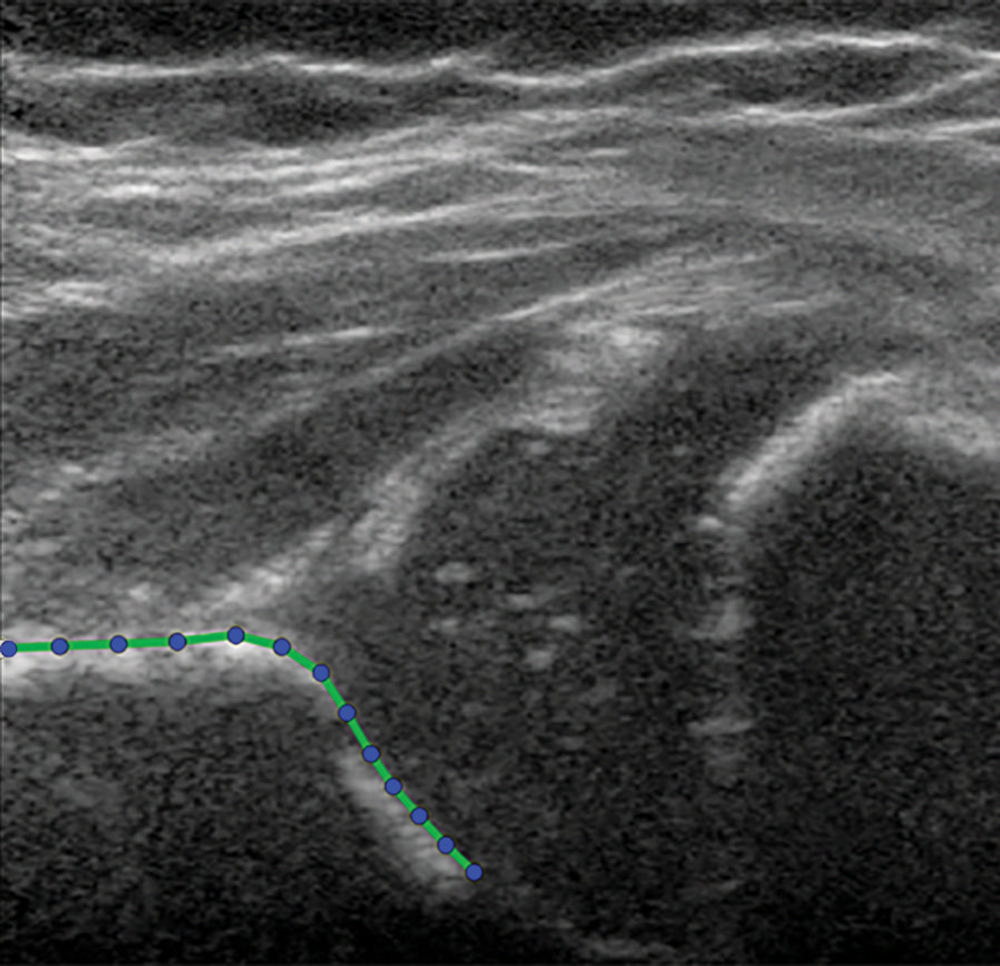

Figure 2. Hip US image in a 3-month-old girl at baseline. No contrast material was used. The presented hip is outlined with the acetabular shape model, consisting of 13 points.

High-res (TIF) version